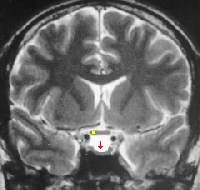

La Silla Turca forma un hueco situado en la vertiente endocraneal del hueso esfenoides.

Su nombre no es casual, pues tiene una curvatura asemejándose al asiento de una silla, con la forma exacta para cobijar y servir de alojamiento a un órgano clave en la regulación de las hormonas: la hipófisis.

Las 4 apófisis clinoides se encuentran en las 4 esquinas del surco hipofisiario.

adelgazamiento de glandula hipofisaria con ocupacion de silla turca por liquido cefalo raquideo. Silla turca vacia

adelgazamiento de glandula hipofisaria con ocupacion de silla turca por liquido cefalo raquideo. Silla turca vacia. Que significa esto en un informe de resonancia magnerica